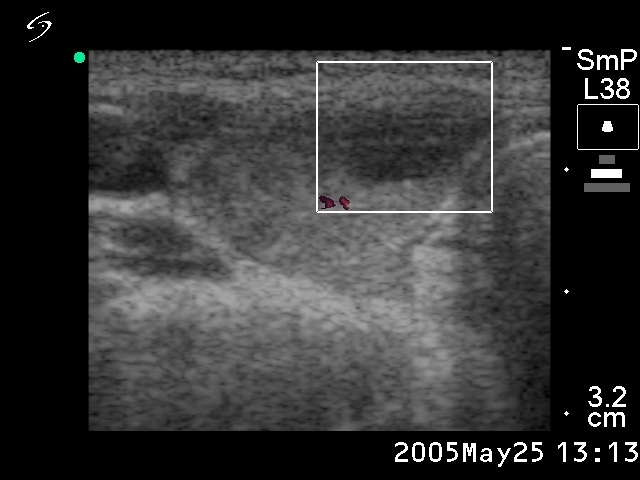

Ultrasonography: the thyroid was minimally hypoechogenic. Two hypoechogenic lesions were found in the right lobe. The larger one contained microcalcifications. There was neither perinodular nor intranodular blood flow.